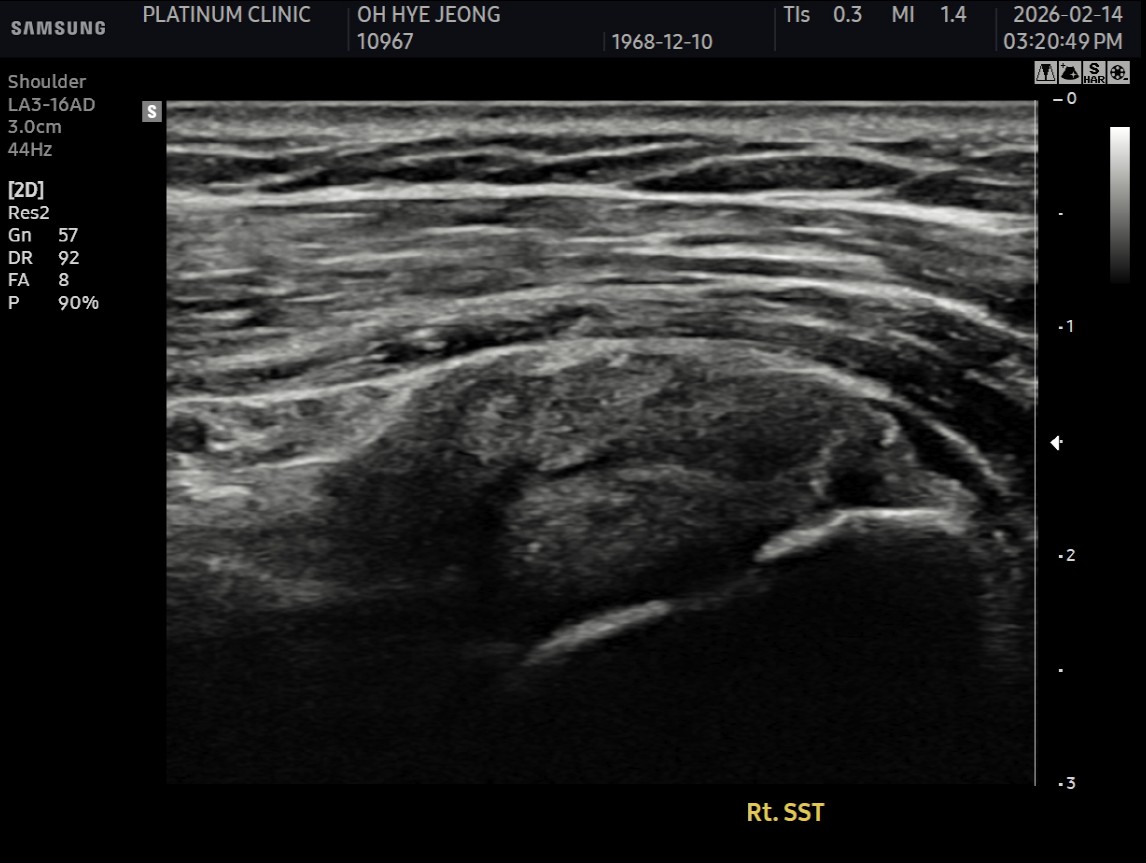

Step 2: 손상 부위 확인

초음파로 점액낭면 파열 부위를 정확히 확인합니다.

파열 위치, 범위 확인

인대 두께 측정

초음파 유도 하에 정확한 위치에 부착

초음파로 패치 위치 확인